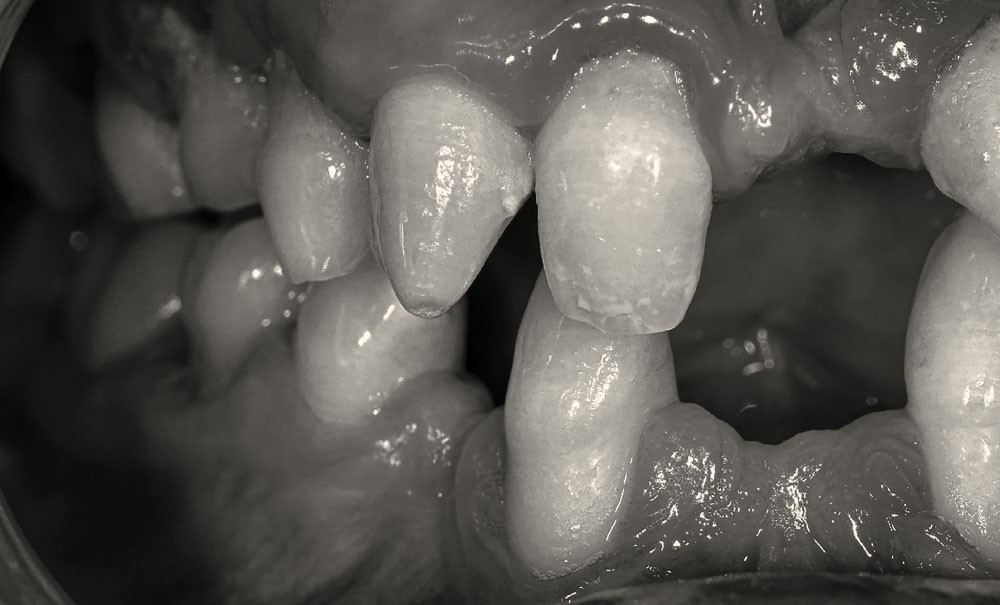

Les maladies rares orales et dentaires, mais aussi de l'os et du cartilage, ont des répercussions bucco-dentaires souvent difficiles à gérer pour le praticien, d’autant qu’elles se manifestent depuis le plus jeune âge. Cet article s'intéressera aux anomalies de nombre, de taille, de forme et de structure dans les cas d'amélogenèse et de dentinogenèse imparfaites.

Les anomalies dentaires surviennent fréquemment dans un certain nombre de troubles génétiques et constituent des signes majeurs dans le diagnostic de ces troubles. Les répercussions au niveau dentaire revêtent différentes formes et peuvent être isolées ou multiples. On distinguera :

• les anomalies de structure (émail, dentine et cément) ;

• les anomalies de teinte.